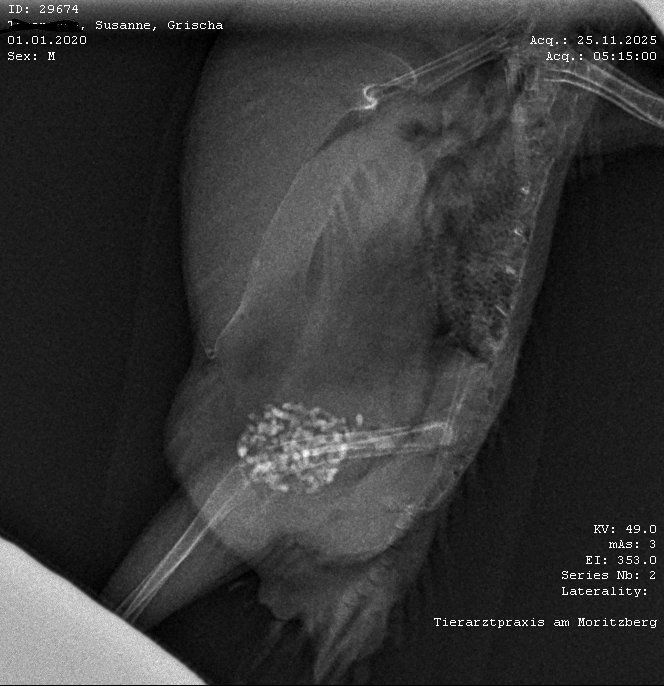

Grische4ka Опубликовано 27 ноября, 2025 #1 Опубликовано 27 ноября, 2025 Здравствуйте, помогите пожалуйста разобрать рентген. Заметны ли какие то изменения? Волнистик быстро и тяжело лишит. Паразитов и бактерий в помете нету. Но очень важно понять есть ли проблемы с внутренними органами. Заранее спасибо!

Grische4ka Опубликовано 29 ноября, 2025 Автор #2 Опубликовано 29 ноября, 2025 Малыш с сегодняшнего дня дергает крыльями. Как бы не умер...